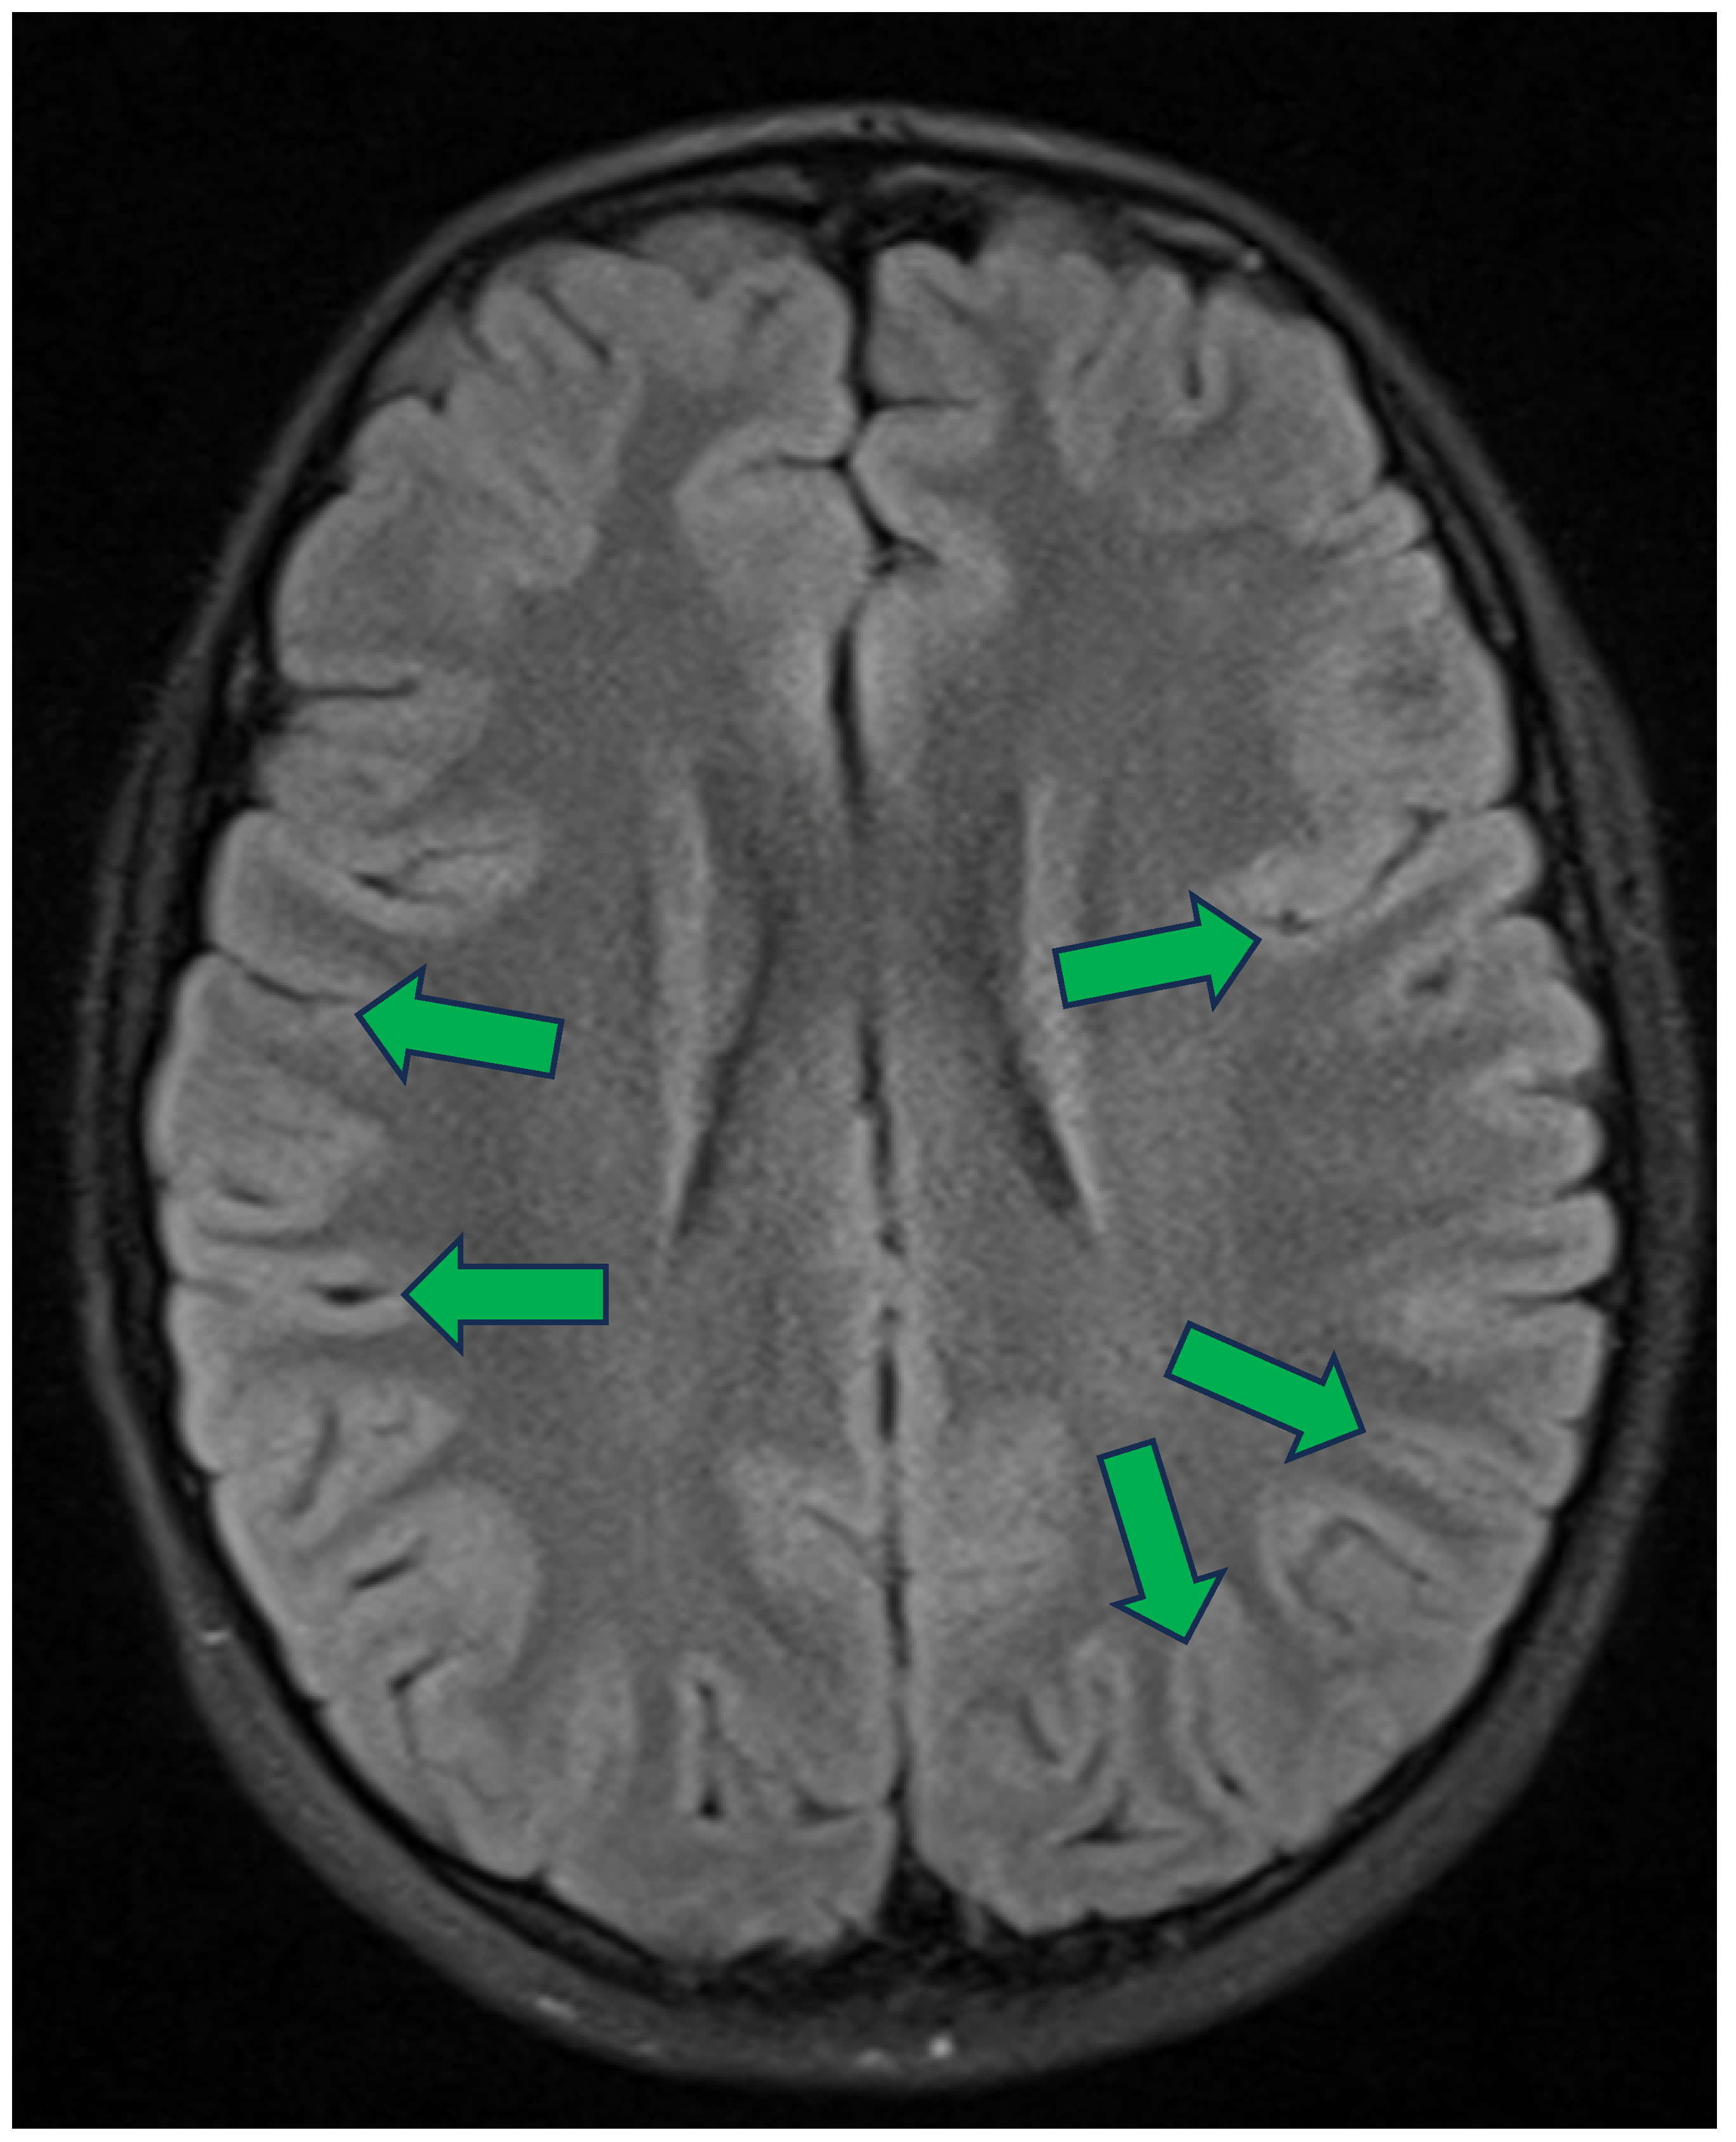

- Bickle, I. Normal MRI Brain with MRV: Teenager. In Radiopaedia.org; 2016. Available online: https://radiopaedia.org/cases/normal-mri-brain-with-mrv-teenager-1 (accessed on 6 April 2025).